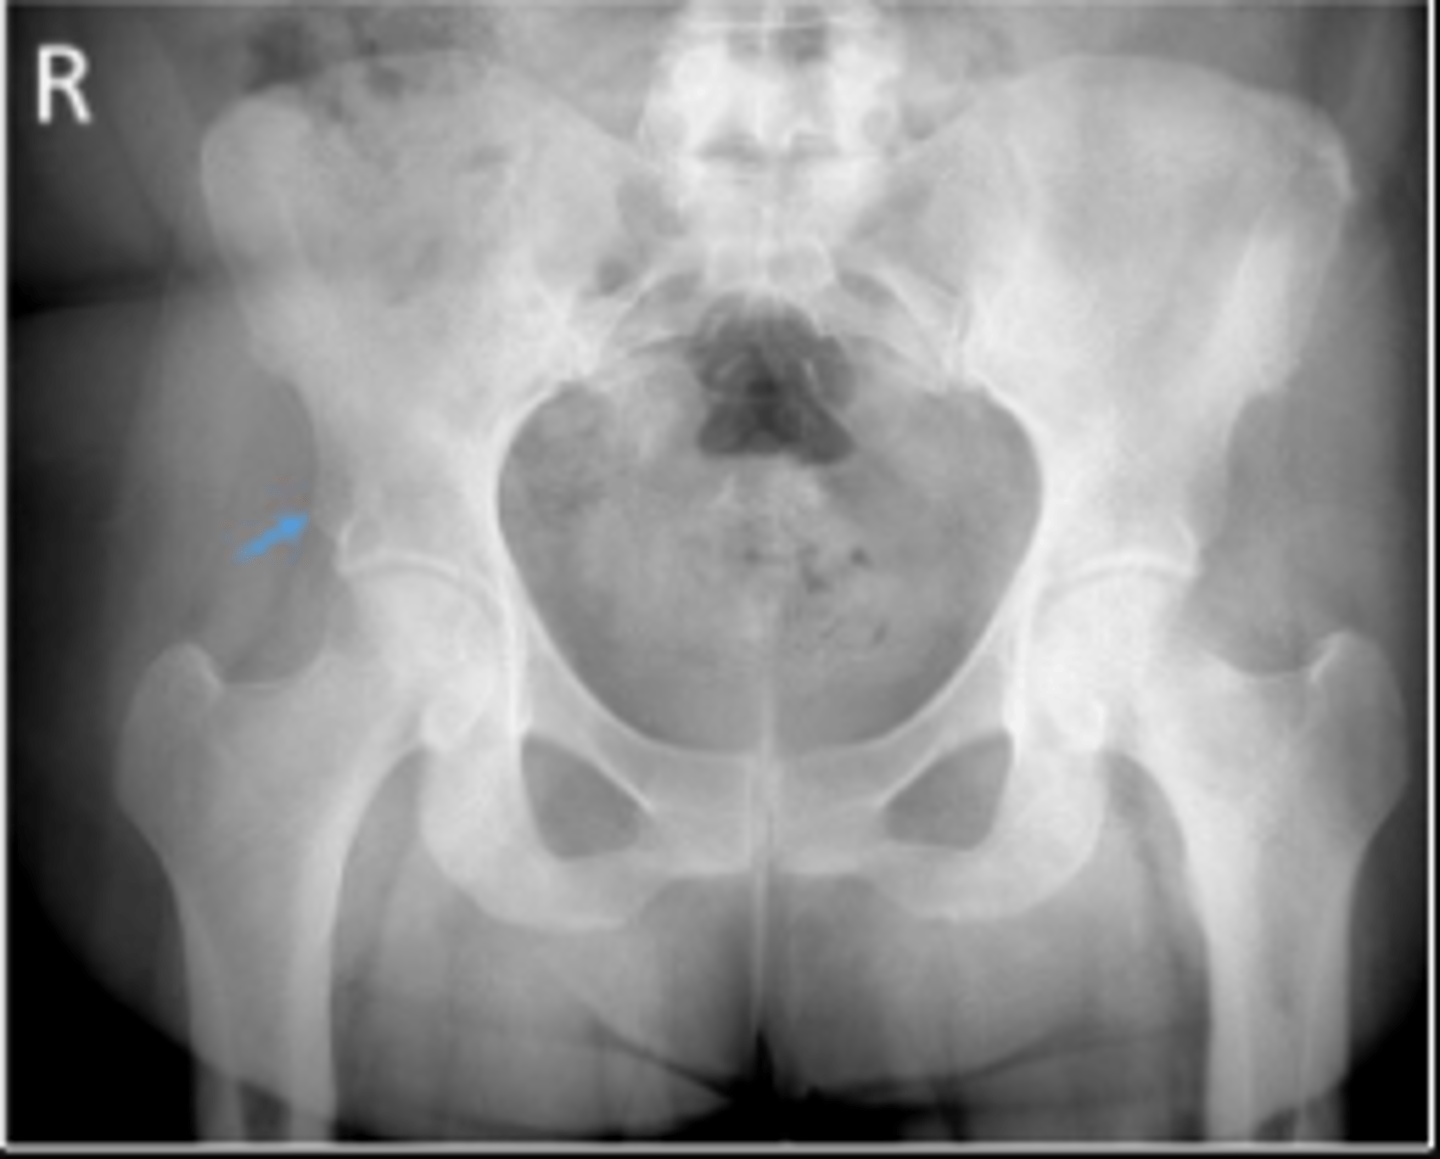

AP pelvis or bilateral hips

What is the name of the radiographic view?

Iliac crest

What are the arrows pointing to?

ASIS

Right sacroiliac joint

What joint space are the arrows pointing to?

Pubic symphysis

What joint space is the arrow pointing to?

Proximal lateral cortical outline of the diaphysis of the right femur

Right pelvic teardrop

What is outlined?